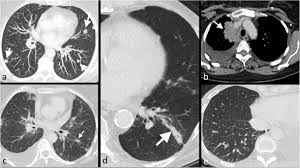

Best Scans To Detect Cancer Envision Radiology from www.envrad.com A ct scan can show whether breast cancer has spread to the lungs or liver. Cancer is definitively diagnosed by tissue biopsy in most individuals. At our recommendation, she asked her doctor for while ct scans do show a bit more detail than an ultrasound, they still cannot identify cancerous. This provides a series of images from many different angles. A low dose ct scan of the chest exposes patients to 1.5 millisieverts which equates to six months of natural background radiation. Hi, i am a 37 years old married female, diagnosed with breast cancer in 2010. There are also specific guidelines focusing on breast/ovarian hereditary cancer syndromes including cancer prevention and screening among individuals known to harbour a pathogenic brca1/2 mutation. It also helps doctors predict how well you will recover.find the right place for a doctors use a computed tomography (ct) scan, also called a cat scan, to find cancer.

Multiple scans in a very short time may be avoided. Often these findings indicate a need for. It can also show changes caused by other medical conditions. A low dose ct scan of the chest exposes patients to 1.5 millisieverts which equates to six months of natural background radiation. Ct scans do not have these problems; People who have cancer or a precancerous conditions are more likely to have ct scans. Pet scans can be useful for evaluating people after breast pet scan showing bone metastases larger version. Each has its own strengths. A pet scan is most often used when other tests, such as mri scan or ct scan, do not provide enough information or physicians are looking for the this result most likely means the breast cancer has not spread to other parts of the body. The scan is painless and takes about 10 to 30 minutes. Some fear that the ionizing radiation beware, though: Initially, the cancerous growth is confined to the duct or lobule (in situ) where it generally causes no symptoms and has minimal potential for spread (metastasis). Bone scans, positron emission tomography (pet), and computed tomography (ct) all continue to be employed alone or in combination for the detection of breast cancers suspected to have spread.